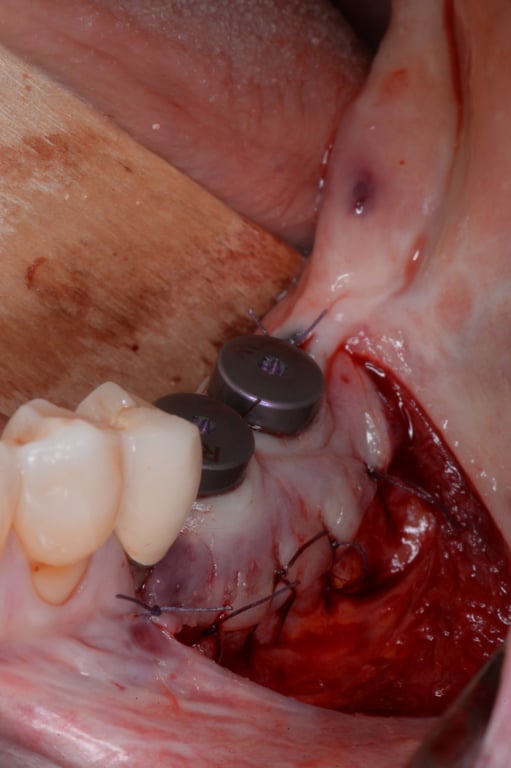

Figure 8.

Exposure of the implants in the third quadrant by stab incision combined with vestibuloplasty according to Kazanjian

Figure 9.

Exposure of the implants in the fourth quadrant by stab incision combined with vestibuloplasty according to Kazanjian